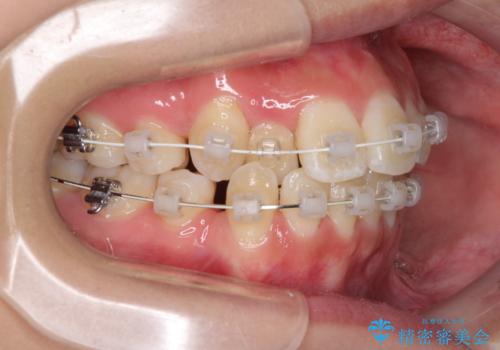

前歯の正中のズレを改善 目立たないワイヤー装置での抜歯矯正

- 八重歯を気にして来院された患者様です。

上下ともに前突感と叢生が認められ、上顎の正中が著しく右側にずれていたため、上下左右第一小臼歯4本を抜歯し、ワイヤー矯正にて治療を行うこととしました。

移動量が多かったため、治療期間は通常より半年~1年ほど長くかかりましたが、上下の正中をほぼ同じ位置にまで移動させることができました。